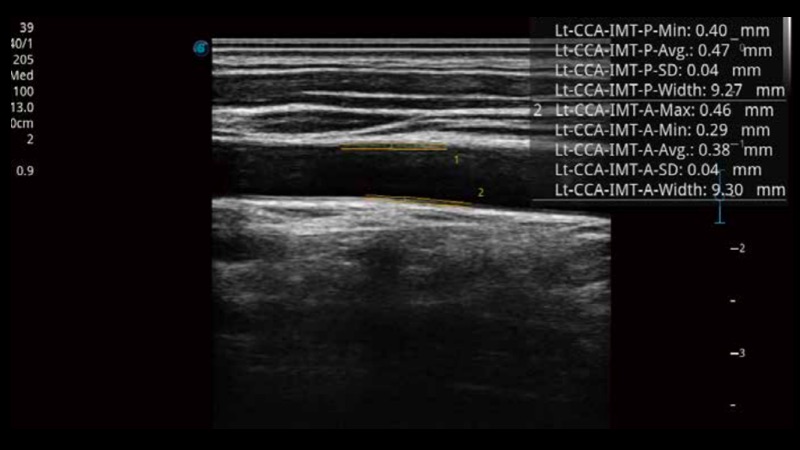

自動(dòng)識(shí)別前后壁內(nèi)膜厚度,為心血管疾病早期評(píng)估提供快速準(zhǔn)確依據(jù)。